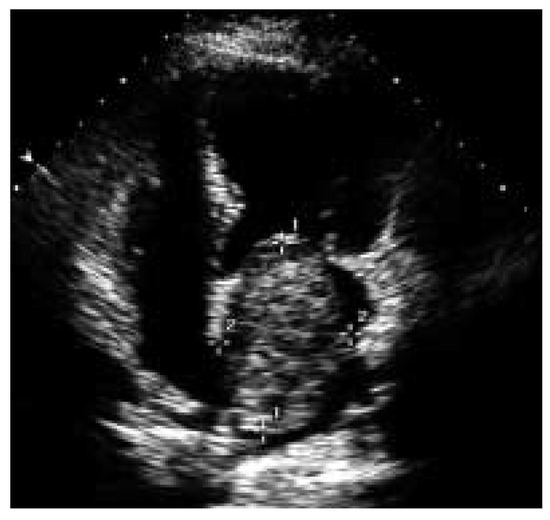

Platypnoe—Orthodeoxie: Eine Seltene Ursache Einer Lageabhängigen Dyspnoe und Arteriellen Hypoxämie

by Urs N. Dürst, Manfred Ritter, Beat Walder and Franz R. Eberli

Cardiovasc. Med. 2005, 8(10), 370; https://doi.org/10.4414/cvm.2005.01130 - 28 Oct 2005

Platypnea—orthodeoxia: a rare cause of positional dyspnea and arterial hypoxaemia. We report a case of an 83-year-old female patient, that developed positional dyspnea after a fall complicated by a thoracic spine compression fracture. In upright position the dyspnea was disabling occurring already with [...] Read more.

Platypnea—orthodeoxia: a rare cause of positional dyspnea and arterial hypoxaemia. We report a case of an 83-year-old female patient, that developed positional dyspnea after a fall complicated by a thoracic spine compression fracture. In upright position the dyspnea was disabling occurring already with normal daily activities, such as dressing. The dyspnea could be relieved by recumbancy. In supine position the patient’s arterial saturation was 94% and decreased to 86% in upright position. Transoesophageal echocardiography revealed an atrial septal defect with bi-directional shunt. The atrial septal defect was closed percutaneously with an Amplatzer-Septal-Occluder® 20 mm. Following the occlusion of the atrial septal defect, arterial oxygen saturation remained stable and the positional dyspnea disappeared. Full article